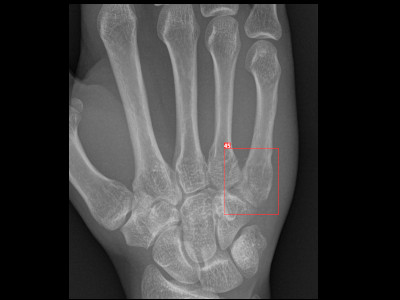

Detecção de fratura do quinto metarcapo em Raio X

Fratura do quinto metarcapo